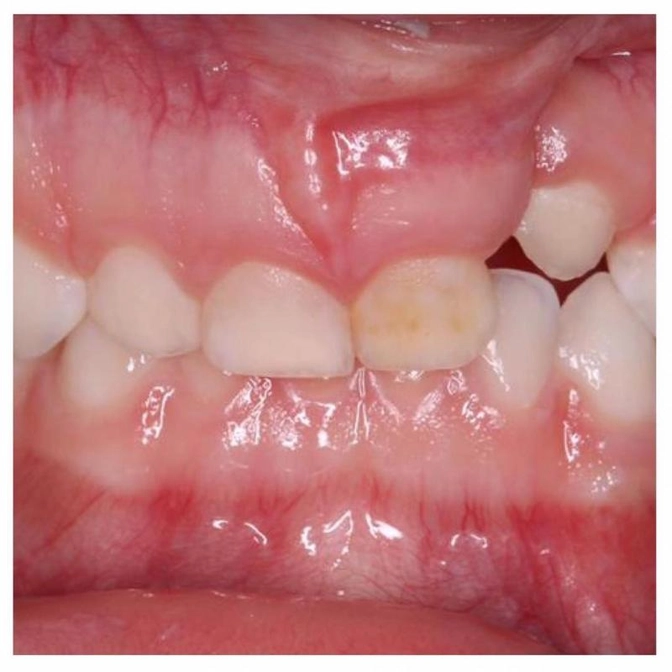

Называется - левосторонняя расщелина верхней губы, альвеолярного отростка, мягкого нёба.

Эта девочка ходит ко мне на профосмотры с двух лет.

Мы уже ставили ей пломбы, в это посещение проводили чистку.

После предстоящих операций она направится к ортодонту, т.к. есть проблемы с прикусом, и зуб, который не в ряду, нужно будет ставить на место.

Желтый передний зуб - это кариес в стадии пятна.

Мы следим за ним, стабилизируем и проводим фторирование.